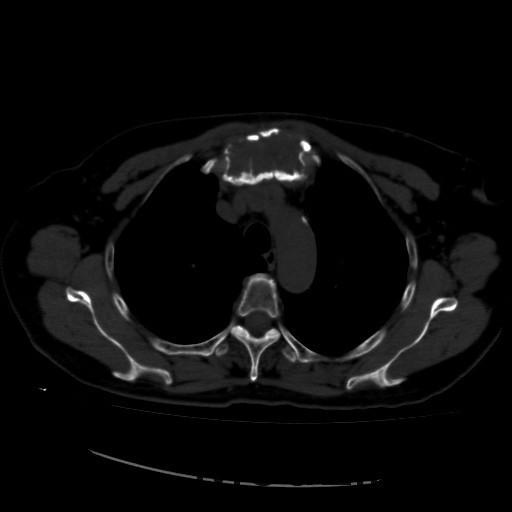

诊断:甲状腺恶性肿瘤(术后);手术后甲状腺功能减退。 治疗:入院时甲状腺球蛋白>455pmol/L,甲状腺素2.793uIU/ml,根据病情于2014-6-3予大剂量碘-131 100mCi清甲治疗;2014年6月全身碘扫示:全身多发异常摄碘组织,考虑甲状腺癌术后双侧甲状腺组织及锥状叶残留并全身多发骨转移。2014年9月胸部CT示:1、双肺多发转移瘤,并胸骨转移;胸1、8、10、腰1椎体内多发结节灶,考虑转移瘤可能性大。2、右肺中叶内侧段、双肺下叶散在慢性炎症。2014年12月全身碘扫:1.全身多处异常摄碘组织,考虑多发骨转移瘤。又于2014年12月复查甲状腺球蛋白抗体90.400U/mL,促甲状腺素6.914uIU/ml。遂于2014-12-22口服250mCi大剂量放射性碘-131。治疗后全身碘扫复查结果提示:2.左肺下叶摄碘组织,不排除转移瘤,建议进一步检查。与2014.6.6检查相比,颈部甲状腺部位放射性浓集灶消失,余病灶放射性浓集程度较前稍降低。

患者又于2015年10月胸部CT复查,结果提示:1、甲癌术后改变;双肺多发转移瘤,大部分病灶较前缩小,左肺下叶病灶较前增多,部分较前增大;胸骨转移;胸1、8、10、腰1椎体内多发结节灶,基本同前,考虑转移瘤可能性大。2、右肺中叶内侧段、左肺上叶舌段及双肺下叶散在慢性炎症。